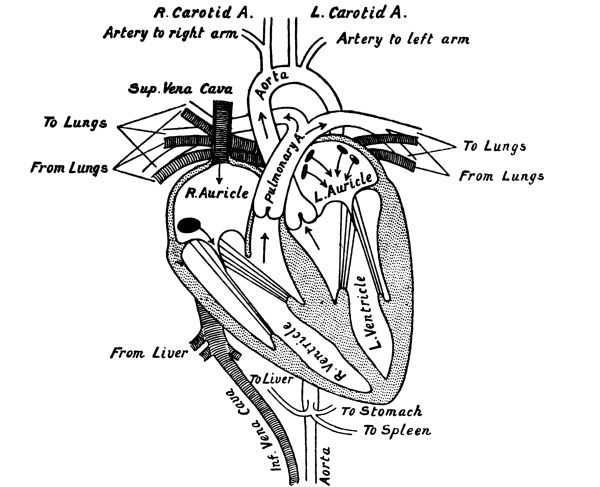

| 10. | The Heart in Longitudinal Section | 218 |

| 11. | Horizontal Section of the Heart, showing its Valves | 225 |